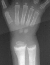

X-RAY STUDIES:

- "cupping" of the distal radius and distal femur

- widening of the physis

- angular deformities